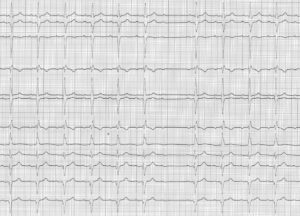

Le BAV du second degré type 2 (Mobitz 2) est beaucoup plus rare que le type 1; les ondes P bloquées non suivies de QRS surviennent inopinément, sans allongement préalable de l’espace PR.

L’électrocardiogramme montre donc:

• Un blocage intermittent de l’onde P; la récurrence des ondes P bloquées peut être régulière mais est le plus souvent irrégulière; le nombre d’ondes P bloquées est généralement majoré par les manœuvres qui augmentent la fréquence cardiaque (effort, atropine) et inversement pour les manœuvres qui la diminuent.

• L’intervalle PR des complexes conduits est constant.

• Les pauses ventriculaires sont de durée double de l’intervalle RR normal.

• Comme chez ce patient, les complexes ventriculaires sont le plus souvent anormaux; plus rarement une morphologie normale (QRS fin) est observée.